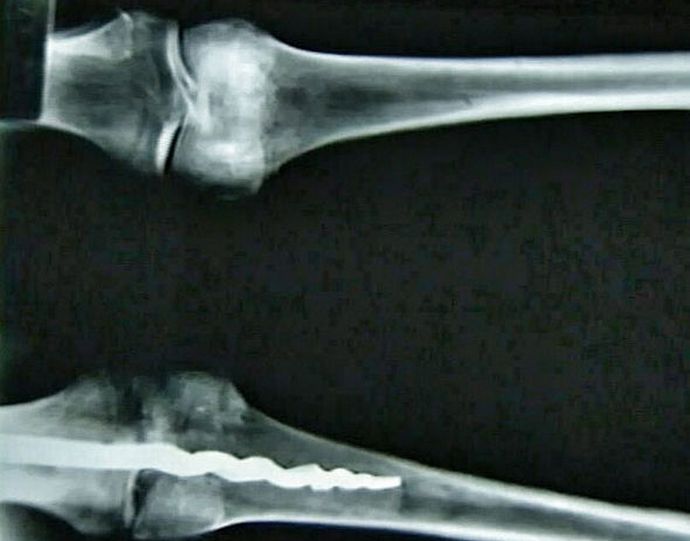

Foto otevřená zdrojová skupina amerických výzkumníků Analýza DNA egyptské mumie v jejím těle shledala skutečnou ortopedický špendlík, méně konstrukční moderní protějšky. Unikátní délka hledání 23 centimetr, ona byla vyrobena z kovu, a její design je jiný výrazná podobnost s ortopedickými kolíky použitými v medicína dnes.

Podle odborníků jsou v koleně člověka starověcí chirurgové dejte čep připevňující kosti a zajistěte jej organické pryskyřice. Udělali to tak obratně a profesionálně, že nejsložitější operace nezanechala žádnou stopu na těle pacienta. Soudě podle objeveného nálezu, metod, používané lékaři v moderní medicíně již dlouho známé našim předkům a úspěšně je aplikují v praxi.

Stále není známo, kdo přesně byl v koleni egyptský což byl objeven úžasný špendlík. Vědci z Ameriky Brigham Young University ho docela náhodou viděla rentgenové paprsky, a poté vyjmuté z těla, trochu překvapené jeho objev.

Nalezená mumie není stará méně než 3000 let, což znamená, že i tehdy starověcí Egypťané měli potřebné znalosti k tomu, aby mohli být konstruováni kolíky schopné opravit správné posunutí kostí pozici a provádění složitých chirurgických operací.

Vědci zatím nemohou vysvětlit povahu tajemného nálezu, obrátili své představy o starověké medicíně. Wilfred Griggs, Vedení výzkumné skupiny, v jejíž rukou se ukázalo jedinečná mumie, přesvědčená, že by jí moc nedal zjistit přesně, jak se egyptským lékařům podařilo vytvořit a umístit tělo muže je takový moderní špendlík.